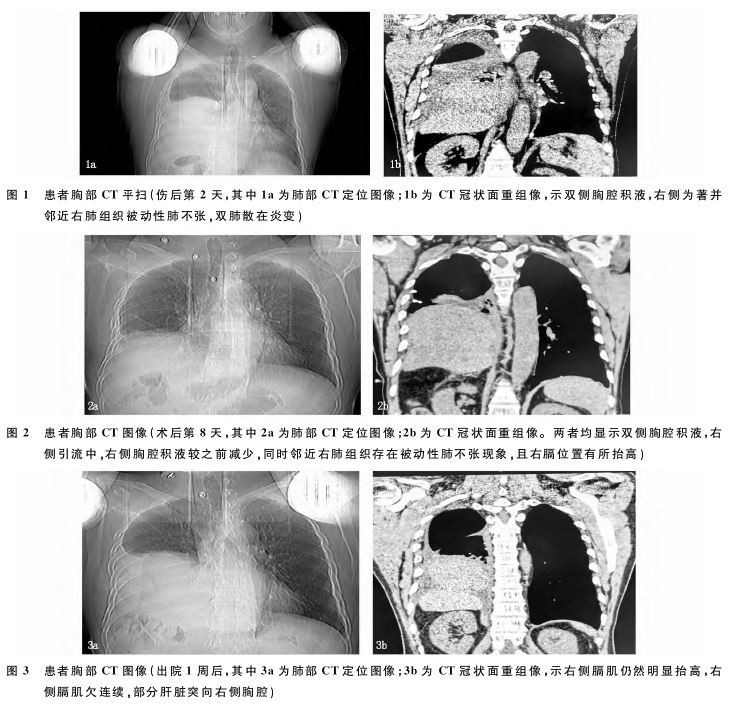

症状略缓解。第2天患者自觉胸背痛及胸闷症状加重,再次来我院急诊,复查胸CT平扫:①左肺舌叶、右肺中叶、双肺下叶少许炎症;②双侧胸腔积液,右侧为著并邻近右肺组织被动性肺不张;③左侧第5~6肋骨改变,见图1。急诊以“胸部外伤、右侧血胸、肋骨骨折”收入院。患者在发病中并无高热症状,也无咳嗽

、咳痰或咳血、大小便正常。住院之后给予右侧胸腔闭式引流术,抗感染、镇痛、对症处理,术后5天共引出约1 200mL淡红色液体,病人自觉右胸憋闷症状减轻。再次复查胸CT:双侧胸腔积液,右侧为著并邻近右肺组织被动性肺不张,较前积液量略减少,左侧第5~6肋骨改变。此时引流管

引出液体已很少,胸科会诊后考虑胸部损伤、继续目前治疗、保持引流管通畅、加强气道管理。调整引流管后陆续又引出400mL淡红色液体,术后第8天再次复查胸CT:双侧胸腔积液,右侧为著并邻近右肺组织被动性肺不张,较前积液量减少,左侧第5~6肋骨改变,右隔肌位置抬高,见图2。再次胸外科会诊:考虑右侧积液量很少,可拔出引流管,因有膈肌抬高避免增加腹压动作。拔管后病人感觉胸部闷痛症状明显减轻,要求出院观察。出院诊断:左胸肋骨骨折、右侧胸腔积液(少量)、腰椎横突骨折、右膈肌抬高待查、腹壁软组织挫伤。出院1周后因右侧胸部闷痛加重遂来我院急诊外科就诊,查胸CT:见右侧膈肌仍然明显抬高,发现右侧膈肌欠连续,部分肝脏突向右侧胸腔,见图3。以创伤性膈肌破裂、创伤性膈疝收入胸外科,补充确切诊断:创伤性膈肌破裂、创伤性膈疝。行膈肌破裂修补术、肝脏复位术,术后6天痊愈出院。